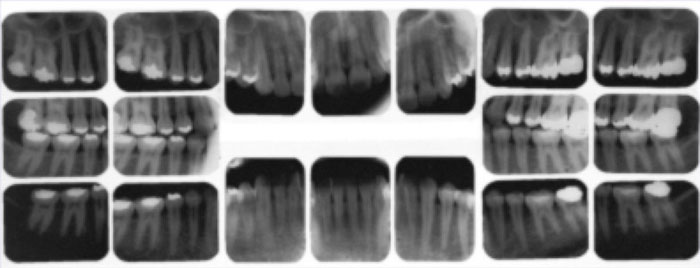

- Complete Series X-Ray is a group of x-rays that shows all the teeth, roots and related areas of the jaws.

Complete series x-ray.